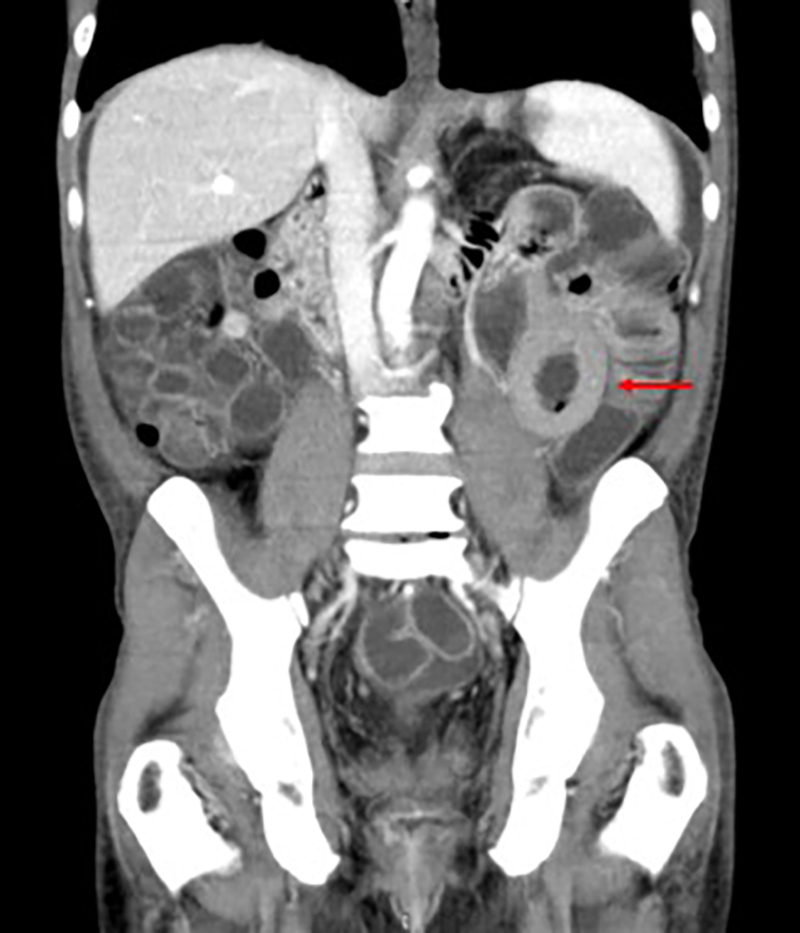

El riñón se compromete principalmente en los casos de trasplante renal, reportándose entre el 10 y 75% de estos casos según variados estudios11,37,40. Las manifestaciones más frecuentes la representan como una masa que rodea el hilio renal, con compromiso subsecuente vascular; y un patrón infiltrativo difuso del parénquima6,11,38) (Fig. 7).

En el caso de una masa renal, esta se presenta con conservación del tamaño renal; mientras que si se manifiesta con un patrón infiltrativo se observará un aumento de tamaño renal con posible extensión extrarrenal y compromiso de órganos adyacentes, permitiendo esto iniciar la sospecha de la entidad38.